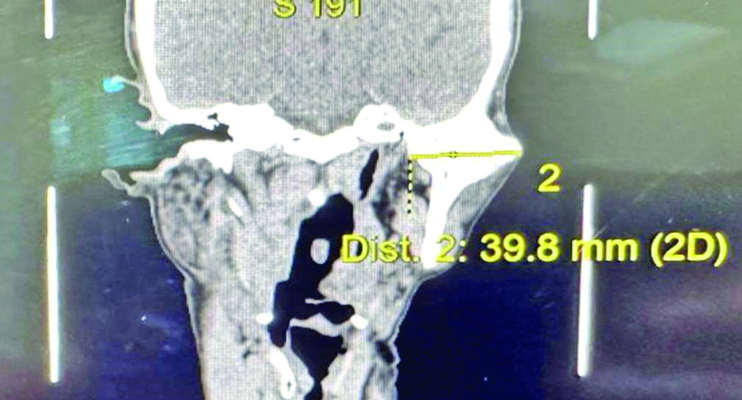

JAMMU: A rare and technically demanding case of temporomandibular joint (TMJ) ankylosis, involving a 4-centimeter bony fusion between the mandibular condyle and the skull base, was successfully treated at the Department of Oral and maxillofacial Surgery, AIIMS Jammu, bringing significant relief and renewed function to an elderly patient who had been living with jaw immobility and pain for years.

The 62-year old patient presented with an inability to open the mouth completely, resulting from a large, abnormal bone mass (approximate size 4 cm) fusing the lower jaw to the skull base-an extremely rare and debilitating form (Type IV Sawhney’s classification) of TMJ ankylosis.